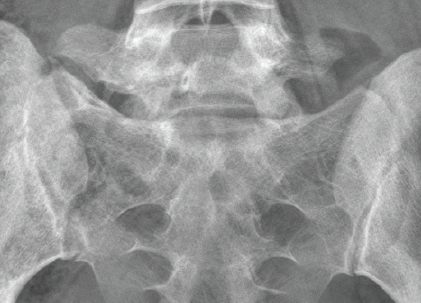

An osteotomy was performed, followed by resection of the fragment, which preserved the L5-S1 joint. Complete resection was confirmed with an intraoperative CT scan (O-arm). Three months postoperatively, the patient presented significant clinical improvement with only occasional lumbar pain in extension exercises, especially during training (Fig. 6).

Figure 6: Lumbosacral X-ray at the 2-year follow-up.